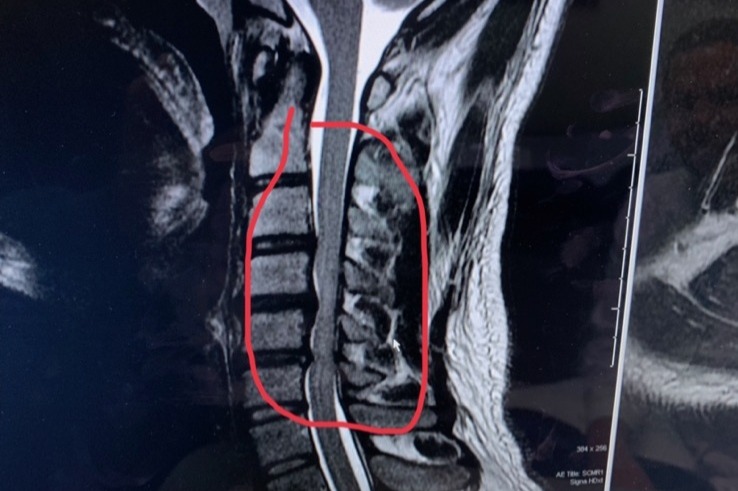

My brother Andrei is a self-employed. He does construction/remodel for the living but due to very unexpected medical condition he will have to undergo a complicated surgery (discectomy) on his spine to replace C2,C3,C4,C5 and C6 disks. - “Anterior cervical discectomy and fusion is a surgical procedure to treat nerve root or spinal cord compression by decompressing the spinal cord and nerve roots of the cervical spine with a discectomy, followed by the inter-vertebral fusion to stabilize the corresponding vertebrae”.

For about 2 years he noticed that he could not keep the balance with closed eyes when he is standing, but for over a year he started feeling numbness on his right side of the body. Strength in his arms and legs is being lost. He started seeing massage therapist and for a short period of time he saw the improvement but not for too long. Finally on June 24, 2019 he was forced to see a neurologist due to severe numbness all over the body, hard to keep balance and nerve pain. Andrei wanted to postpone the surgery to a later time but on September 24th he had a follow up appointment where doctor informed him that he is at a high risk to be paralyzed and the surgery needs to be done ASAP.